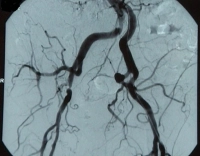

Filmbeispiel: TASC B, hochgradige Stenose der A. iliaca externa und 50 %ige Stenose der A. iliaca communis rechts, klinisch AVK Stadium IIb nach Fontaine → Indikation zur endovaskulären Rekonstruktion